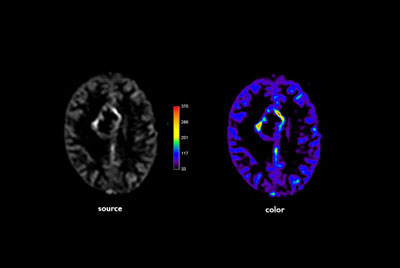

Brain lesions with computed DWI